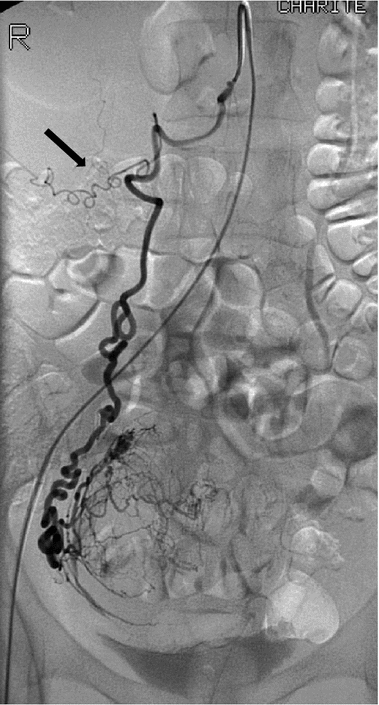

![]() 双侧子宫动脉发育不良 双侧卵巢动脉栓塞术 - 500 - 900 微米 未出现卵巢功能衰竭 ![]() 约10%-15%的患者在接受UAE后未见明显改善,其中一些病例可能是因为卵巢动脉提供了额外的血供。 文章通过回顾六例患者的治疗经验,探讨了卵巢动脉栓塞术(OAE)作为子宫动脉栓塞术(UAE)补充疗法的可行性和效果。研究发现,OAE能够成功地使肌瘤缺血坏死,并且大多数患者在术后症状有所改善。尽管存在技术挑战,但OAE似乎是安全有效的。此外,所有接受OAE治疗的患者均保留了正常的月经周期,这表明该手术可能不会导致卵巢功能丧失。然而,由于样本量较小,目前的研究结果尚不足以得出明确结论,需要进一步的研究来验证这些发现。 ![]() 评估在有卵巢动脉参与供血的症状性子宫肌瘤患者中,进行卵巢动脉栓塞术的安全性及临床结局。 共13名患者,均有症状性子宫肌瘤,且MRI或血管造影显示有卵巢动脉参与供血。并在初次或二次进行补充卵巢动脉栓塞术。

所有年龄超过 40 岁的患者, 卵巢受损 14%-43% 研究中闭经发生率(15%)与单纯UAE报告相似,可能与患者年龄(≥45岁)及卵巢储备自然下降有关。 ![]() 50岁,长期因子宫肌瘤导致月经出血过多,痛经和贫血。 子宫肌瘤栓塞术前,显示双侧子宫动脉发育不全,子宫肌瘤双侧卵巢动脉。 经皮股动脉穿刺双侧卵巢动脉栓塞,先500μm-700μm emboSphere 微球 术后4周,和6月的中短期随访,月经正常,子宫容积减少,贫血纠正,无卵巢功能衰竭。但看起来非灌注容积较少。 术后9月,由于子宫肌瘤持续存在,患者自己希望绝经,行全子宫和双侧卵巢切除术 术后病理,子宫内可见栓塞微粒伴有坏死,卵巢内也见栓塞微粒,但卵巢功能未受损。